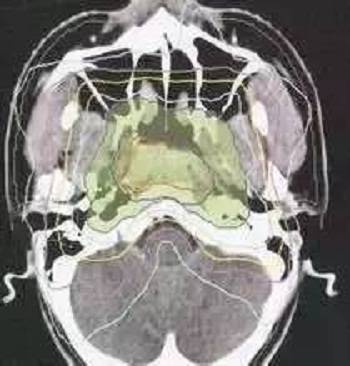

同时,放疗医生根据影像学图像,确定需要照射的范围,逐层勾画靶区,这个包括了影像上可见的肿瘤区域(GTV)及潜在可能累及的区域(CTV)。

并且考虑入肿瘤随呼吸的运动(ITV)及其每日接受放疗时候的摆位误差可能的影响(PTV)。精确的靶区勾画是精准放疗的重要保障。

IMRT: Intensity Modulated Radiation Therapy, 调强放疗,根据照射部位(靶区)的三维形状, 射线从多个不同的角度进行照射,每个角度的射线强度和射束形状都相应调整,使射束形状与肿瘤形状匹配,同时使得靶区内剂量均匀。